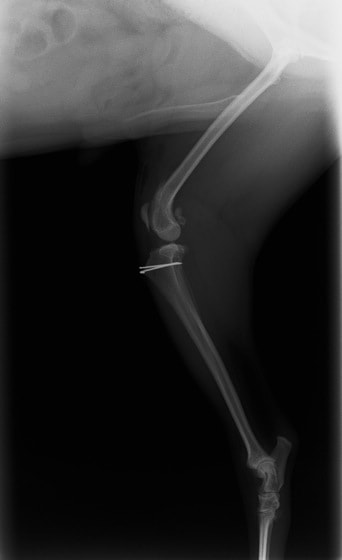

■ 症例24 キャバリア 7か月

左右膝蓋骨内方脱臼(左:グレードⅣ 右:グレードⅢ)

以前から左右後肢の跛行が認められ、整形外科学的検査・レントゲン検査により左右の膝蓋骨脱臼が認められた。症状が重度である左膝の膝蓋骨脱臼整復術を行った。外科手技は縫工筋及び内側広筋の解放、脛骨粗面の外側転位、滑車ブロック形造溝術、内外側関節方の縫縮を実施した。術後一か月時点で、左の膝蓋骨は安定しており経過は良好である。

本症例は成長期における重度の膝蓋骨脱臼であり、術後の再発の可能性もあるため、経過をしっかりと観察していく必要がある。また、今回手術を実施していない右膝に関しても経過を観察し、手術を検討していくこととする。